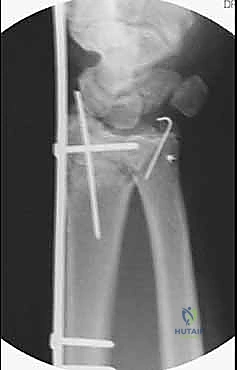

تعتمد هذه التقنية المتقدمة على مبدأ إبقاء المفصل مشدوداً ومثبتاً من الخارج. الصفيحة تعمل كـ "جسر" يعبر فوق منطقة الدمار الشامل في العظم، وترتكز على عظم سليم في الساعد وعظم سليم في اليد. هذا الجسر يمنع العظم المفتت من الانهيار ويسمح للشظايا الصغيرة بالالتئام في مكانها الصحيح بفضل الشد الطبيعي للأربطة المحيطة.

5. وضع البراغي النهائية (Screw Insertion)

يتم تثبيت الصفيحة بقوة باستخدام براغي متطورة (Locking Screws) في عظم الساعد السليم وعظم المشط في اليد. هذه البراغي تلتحم بالصفيحة لتشكل هيكلاً صلباً للغاية لا يتأثر بالحركة.

6. التحقق الإشعاعي (Fluoroscopic Verification)

أثناء العملية، يستخدم الدكتور هطيف جهاز الأشعة المباشر للتأكد من المحاذاة المثالية للعظم واستعادة الطول والزوايا التشريحية الصحيحة للرسغ.

- بعد 3 إلى 4 أشهر: يكون العظم المفتت قد التأم بالكامل وأصبح كتلة صلبة. في هذه المرحلة، يتم إجراء جراحة صغرى بسيطة جداً (Day Case Surgery) لإزالة الصفيحة الجسرية.